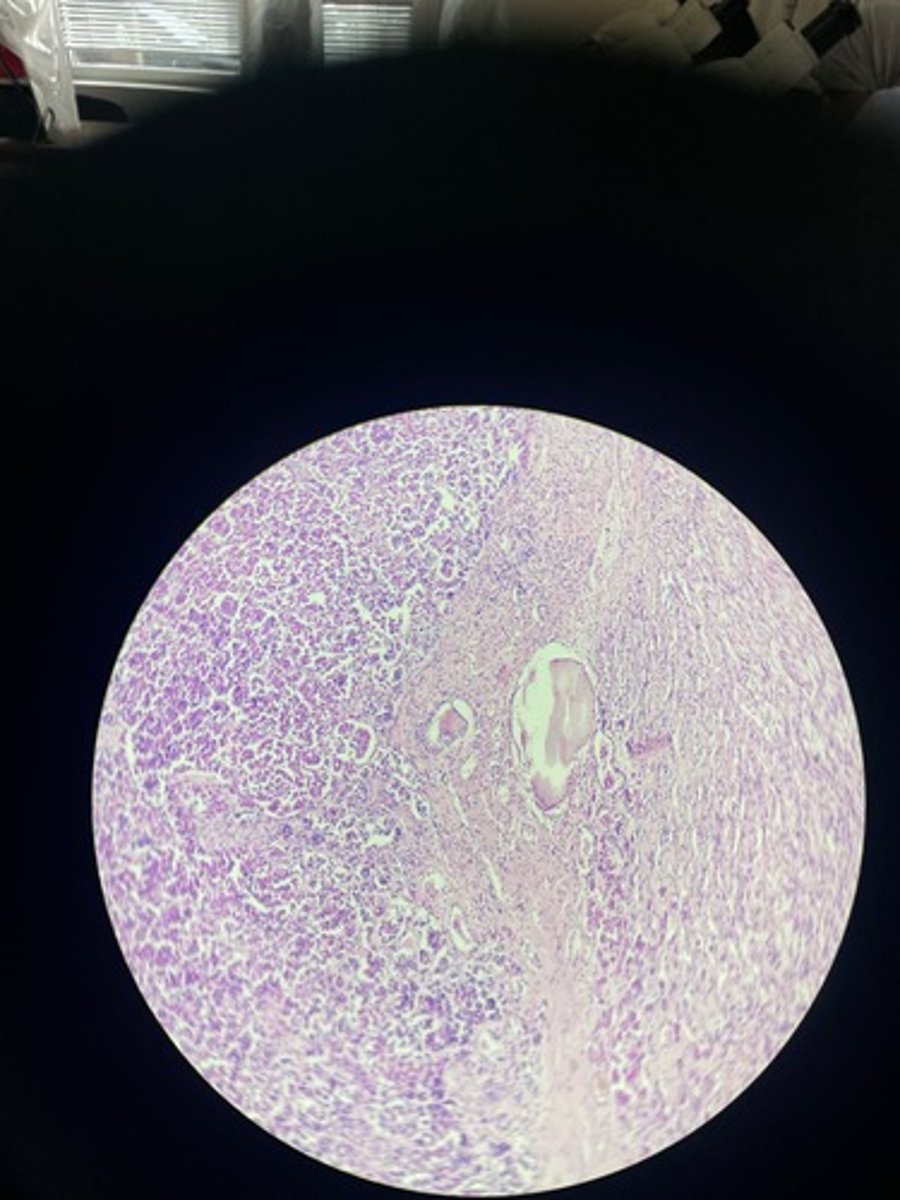

Lymph node HE

Lymph node HE

Lymph node HE

lymph node HE

Lymph node HE

Lymph nodes HE